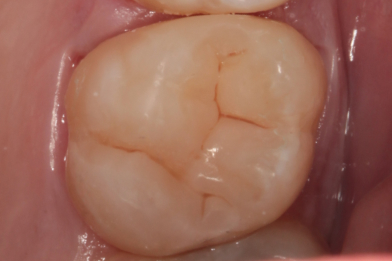

Лечение кариеса 1.7 зуба. Препарирование кариозной полости. Восстановление анатомо-физиологической формы с использованием пломбировочного материала.

Бояринов Сергей Эдуардович -